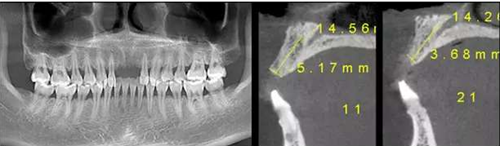

CBCT檢查顯示:水平向骨量不足,無明顯垂直向骨缺損。

2、針對(duì)骨量不足的問題,種植體型號(hào)選擇3.5mm,同時(shí)進(jìn)行外科引導(dǎo)骨再生。

在11、21位置植入兩顆NobelActive 3.5mm*13mm種植體;